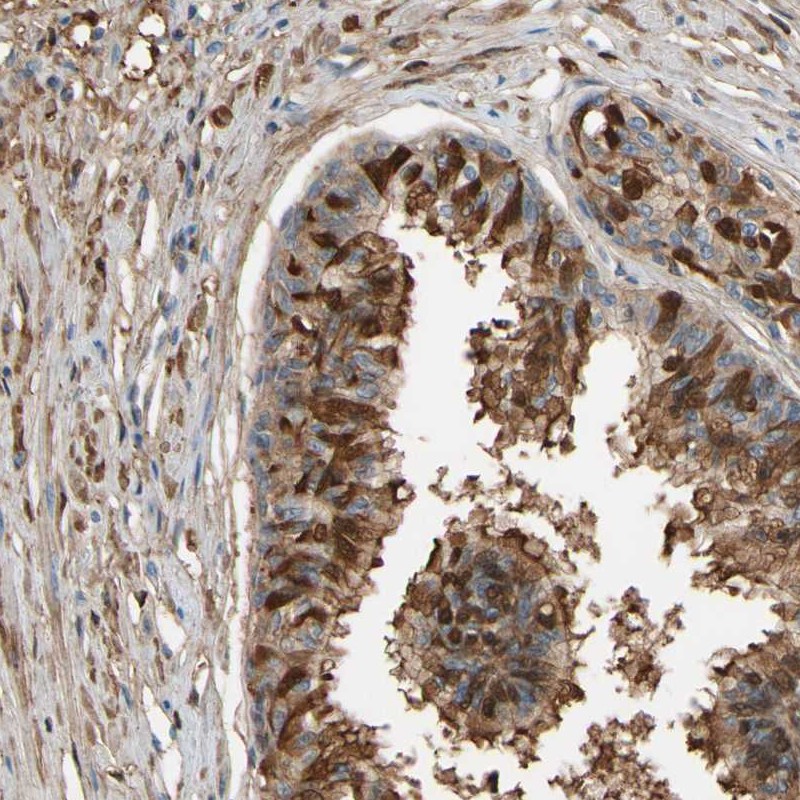

Immunohistochemical staining of human prostate shows strong cytoplasmic positivity in glandular cells.